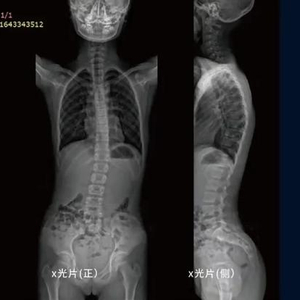

何丹眼下着力的“脊柱侧弯”是一种青少年常见的致残性畸形,它包括冠状位、矢状位和轴位的脊柱锥体排列异常,发病存在隐蔽性。

若缺乏及时干预,脊柱侧弯轻则导致患者躯干、胸廓出现变形,重则产生脊髓和脊神经损伤,形成呼吸系统及心脏功能障碍。

“目前医院常用X光射线检测脊柱侧弯,这是目前医学上最准确的检测方式,但辐射面积相对较大,容易对人的血液系统和生殖系统等造成不可逆的损害。尤其是那些已经发现侧弯或存在侧弯倾向的孩子,为了更好地治疗矫正,他们需要在18岁前持续随访,不停地去拍X光。”何丹解释道。“这样的诊治方式对于孩子而言危害相当大。我曾读过一篇相关研究,数据显示:当脊柱侧弯患者持续随访二十年,他的癌症发病率骤升,达到了普通人的500%。”